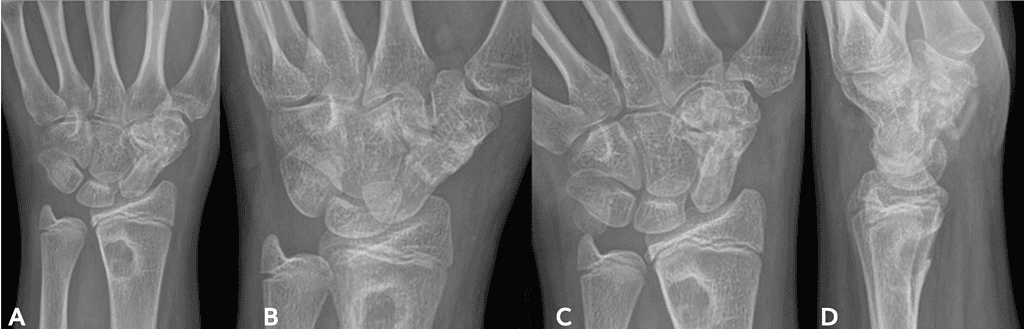

Bone healing across the fusion site was seen as early as 6 weeks from surgery. At the 2-month follow-up, there was clear bone bridging across the fusion site. On her 5-month post-operative visit, her scaphoid-trapezial fusion was fully consolidated at 100%.

Screenshot 2026 01 20 At 2.48.43 Pm Ossio – Naturally Transformative Bone Healing

Figure 4: Revision surgery using OSSIOfiber® Implants 3-Months Post-operative X-rays, taken July 2025;

AP [A] & [B], Oblique [C] and Lateral [D]